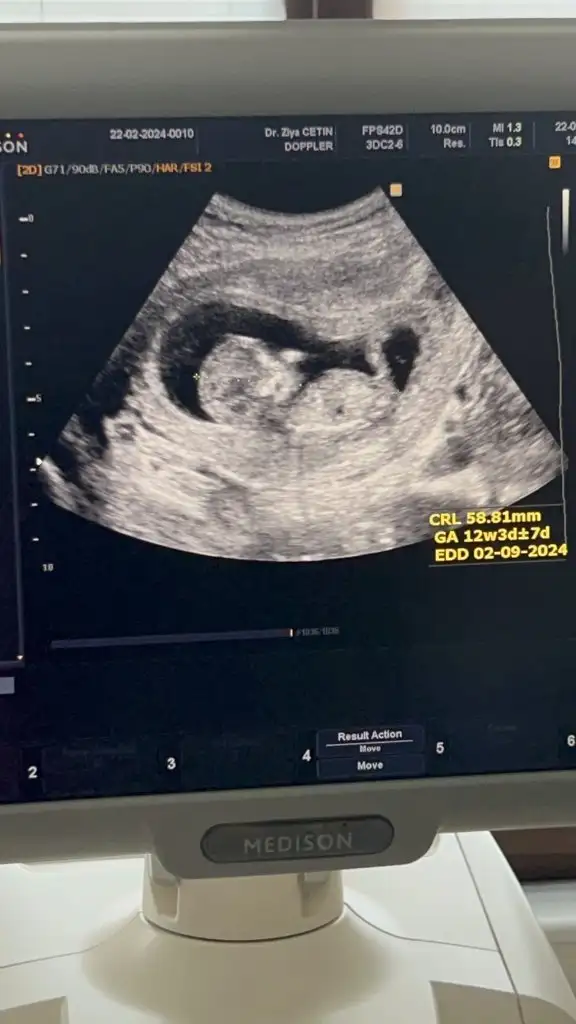

Bu da benimki 14+4 olduk bir bakın kızlar sizce ne doktor belli değil dedi henüz. Bir başka doktor da erkek gibi duruyor dedi bilemedik valaKızlar bebişlerinizin ultrason resimlerini ve cinsiyetini kaçıncı haftada olduklarını yazında kendi ultrason resimlerimizle kıyaslayıp fikirde bulunalım. Nub teorisi, kafa şekli, kemik yapısından cinsiyet teorileri tutuyor mu bakalım bir